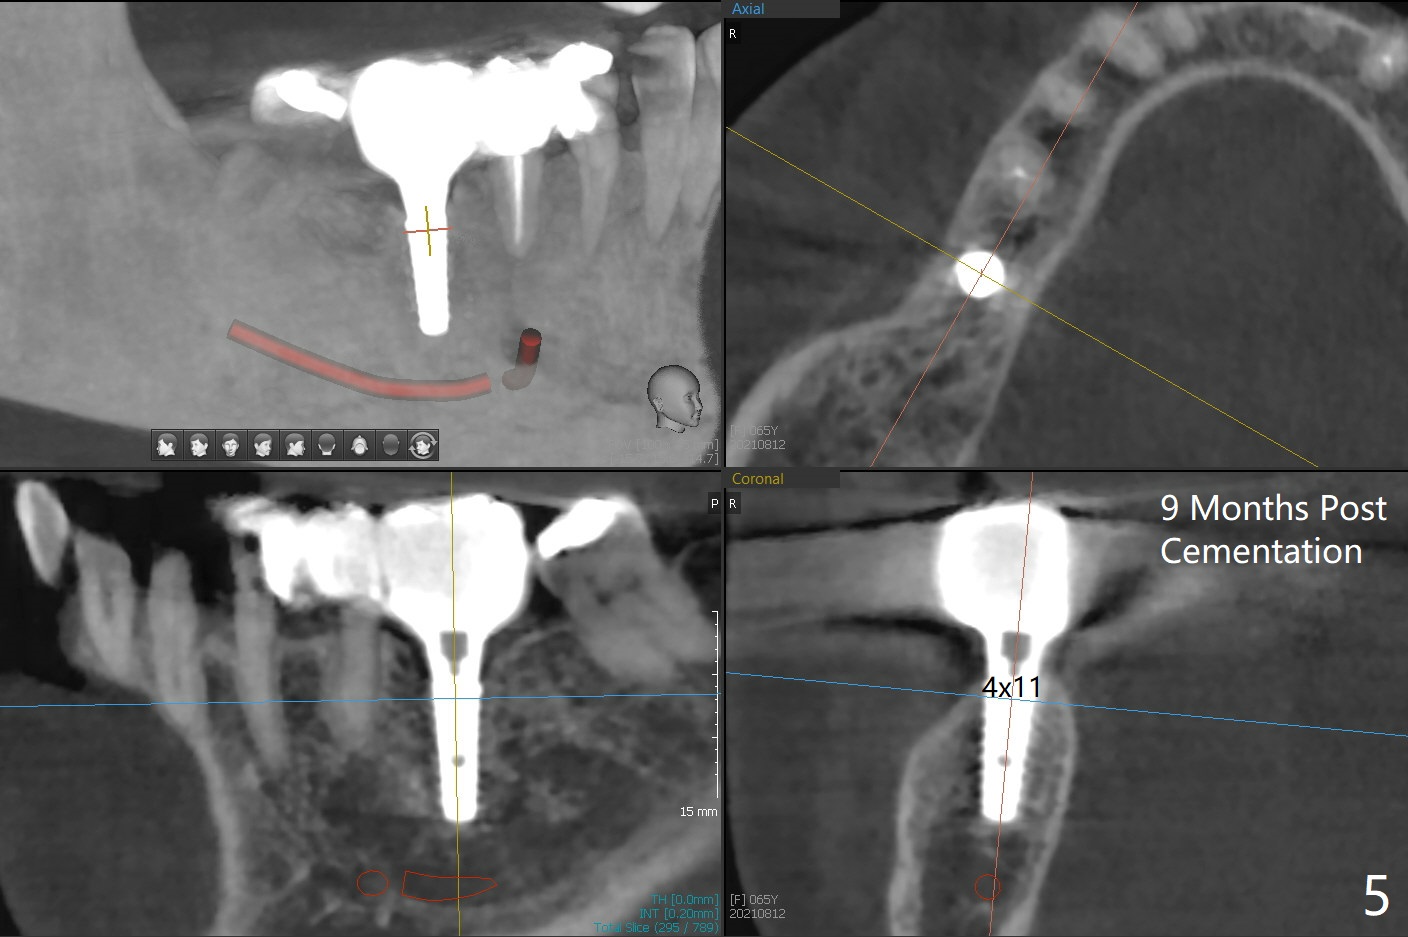

Since the preop ridge looks narrow at #30, incision is made, which makes it easy for observation of osteotomy. First, a 10.5 mm bone trimmer makes a deep dimple with apparently moderate ridge wide enough for a 4 mm implant. The patient has hypertension and cannot lie down for long. The bone density feels not high; a 4x11 mm (instead of 9 mm) implant is placed for 10 mm osteotomy (Fig.1 (~ 35 Ncm)). After use of 6 mm bone profile drill, there is bone buccal (less) and lingual to the implant. A 5.5x4 mm healing abutment is inserted, barely supragingival. As the implant is 1 mm longer than the design, regional panoramic X-ray is taken to determine clearance from the Inferior Alveolar Canal (Fig.2 red dashed line (the upper border). There is crestal bone loss 4 months postop (Fig.3,4). It appears that the implant was placed excessively deep. There is no implant thread exposure 9 months post cementation (Fig.5,6).